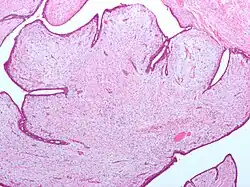

| Fibroepithelial neoplasm (Phyllodes tumor). | |

A fibroepithelial neoplasm (or tumor) is a biphasic tumor. They consist of epithelial tissue, and stromal or mesenchymal tissue. They may be benign or malignant.[1]

- Phyllodes tumor of the breast